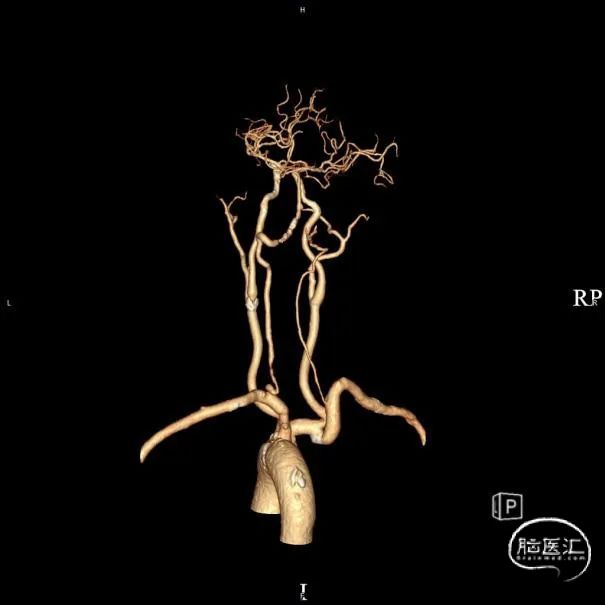

➢头颈部CTA(三维重建MIP像)

➢头颈部CTA(原始像)

患者于入院前10天突发视物重影,5分钟左右缓解,当晚18:00出现颈后不适伴左上肢持续性麻木,10天后来我院急诊神经内科就诊,就诊时测血压191/93mmHg,自行服用拜新同1粒。 完善头颅MRI:桥脑、两侧小脑急性缺血性梗塞;右侧基底节软化灶;两侧侧脑室旁少量白质疏松;老年脑改变。 入院后予药物保守并完善头颈部CTA:左侧颈内动脉虹吸段多发钙化斑块、混合斑块,管腔轻-中度狭窄,C7段小动脉瘤。右侧颈内动脉虹吸段多发钙化斑块,管腔轻度狭窄。右侧椎动脉纤细,V4段局部显示欠清。左椎V1、V2段非钙化斑块,局部管腔重度狭窄-闭塞,V4段钙化斑块,管腔中度狭窄。右侧部分型大脑后动脉,P1段重度狭窄,P2段中度狭窄。双侧大脑中动脉M2段中至重度狭窄。 告知患者病情存在进一步进展可能,患者家属商量后要求手术治疗。

术前影像考虑右侧孤立椎,左侧椎动脉V1段重度狭窄、狭窄段以远扭曲成襻且合并长节段多发动脉粥样硬化狭窄改变(夹层待排),同时左椎V4段局部重度狭窄可能;